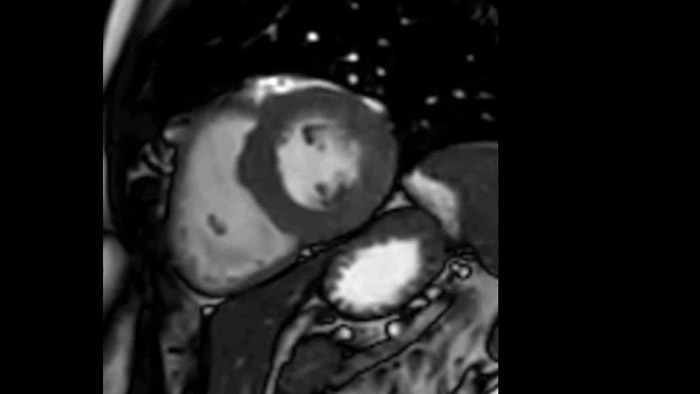

Clinical confidence in cardiac MR

Due to the design of the BlueSeal magnet there is a negligible energy transfer from gradient coil to the magnet. This allows to maintain perfect B0 stability overtime which is especially beneficial for B0 sensitive acquisitions like cardiac bTFE sequences.

Comprehensive cardiac MR imaging

Diagnostic and prognostic utility of cardiac MR is increasing. Assess the anatomy and function of the heart using cine acquisitions, acquire information about perfusion and viability of the cardiac tissue, visualise potential edema with black blood sequence, access and even quantify tissue characterisation with CardiacQuant.